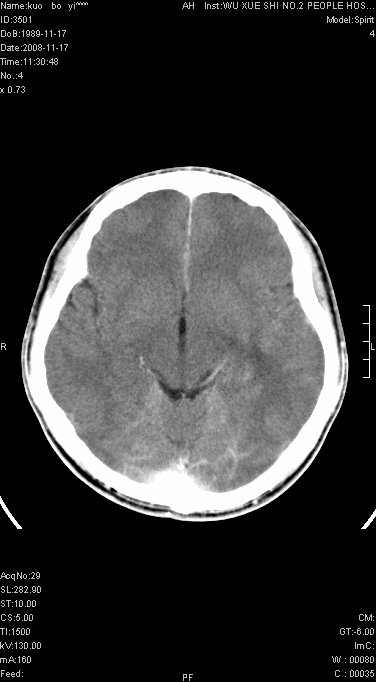

这么大片面积,中线居中,占位效应不明显,考虑脑梗塞。

灶中央有厚环状高密度成分,顶叶皮质局部有显著的受压表现,多支持占位性病变,胶质瘤?淋巴瘤?转移?不知患者年龄多大,病史较短,不除外炎性

增强后水肿中心高密度灶有明显强化,强化不均匀,呈雪花状或絮状,且强化明显,若为肿瘤,应该出现形态较规则的瘤体影,强也有例外如胶质瘤就可以形态不规则.但胶质瘤明显强化者多为恶性间变性,与病史及相关表现太不相符.因此本例多考虑为炎症引起.

考虑左侧顶叶脑炎可能;建议追踪复查。

左顶叶较大范围水肿区,内见明显强化的片状 棉絮状组织,但占位效应不明显。多考虑:脑炎!

还是考虑原发脑胶质瘤,梗塞缺血水肿的低密度要同时累及皮、髓质并要符合动脉供血的区域分界特点,本例强化后见瘤体结节及向周围浸润生长的瘤血管都强化了,水肿广泛呈指状,占位效应使同侧脑皮质受压变薄、脑沟消失但因实质性的瘤体尚小所以中线无明显移位。不知各位同意这样分析吗?(转移瘤多为多处病灶)

首先考虑脑胶质瘤。有明显的左顶叶脑白质水肿,病变轻度占位效应,花环样强化,脑炎——影像不支持!

左顶叶大范围水肿,内见明显强化的片状 棉絮状组织,但占位效应不明显。考虑脑炎可能性大。

在北京天坛医院治疗考虑寄生虫感.明显好转